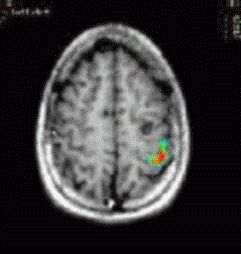

T1 weighted MRI

Transverse image at the level of the planum temporale. The left hemisphere is seen in the right side (radiological convention). The subject's task was listening to a story.The red bubble seen on the left side corresponds to areas related to complex semantic processing.